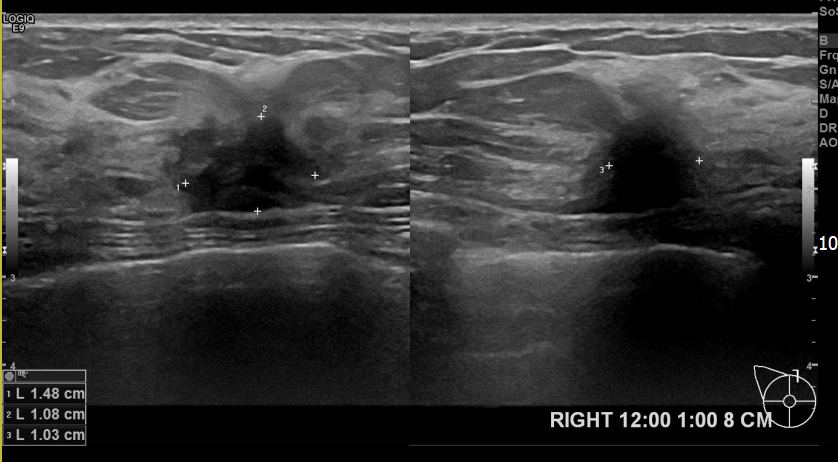

상기환자  우측유방멍울만져져 내원하신 50대여성분으로 조직검사시행후

유방암진단되셨습니다